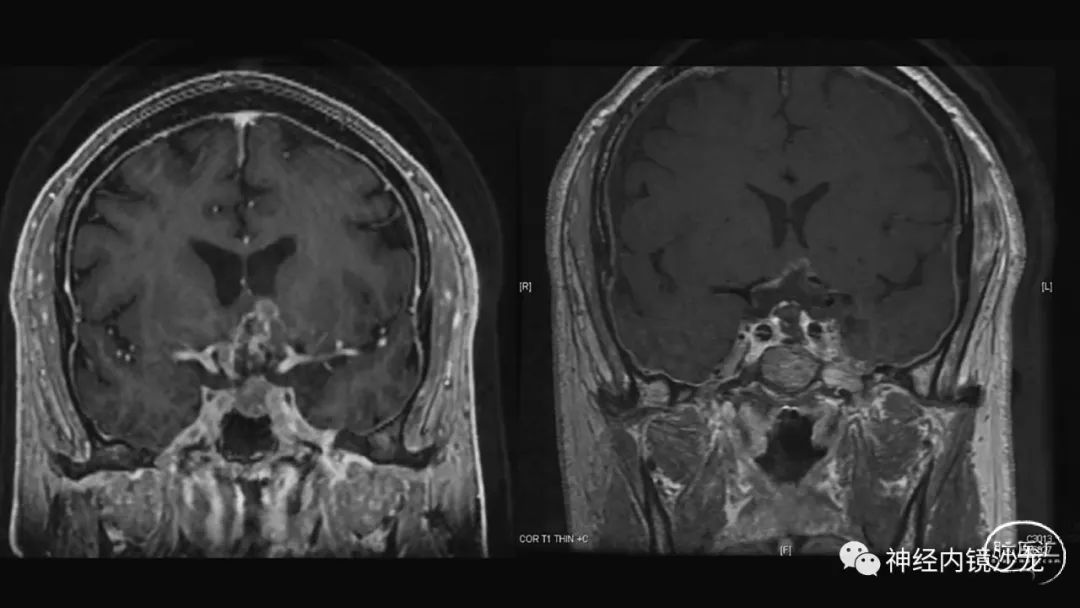

从事神经外科十余年,擅长神经外科肿瘤诊治,尤其是神经内镜微创手术治疗垂体瘤、颅咽管瘤、脑膜瘤等颅底肿瘤